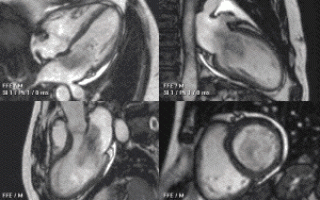

Решающее значение в ходе диагностики данной патологии отводится такому ультразвуковому диагностическому исследованию сердца, как трансторакальная эхокардиография. Если с ее помощью установить диагноз не удалось, назначают чреспищеводную эхокардиографию.

УЗИ сердца позволяет обнаружить объемное образование в сердце, определить его размеры и локализацию, место прикрепления и подвижность ножки.

Для уточнения данных иногда проводят КТ и МТР сердца, артериографию, вентрикулографию, коронарографию.